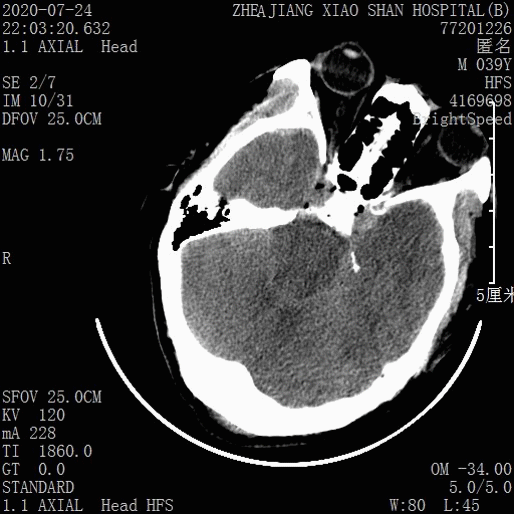

急诊头颅CT:

1.双侧创伤性硬脑膜下血肿

2.脑疝

3.双侧额叶脑挫裂伤

4.枕骨骨折